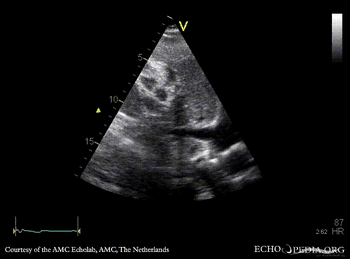

Obstruction of vena cava inferior

Subcostal view: obstruction of vena cava inferior from outside the heart Subcostal view with Color Doppler